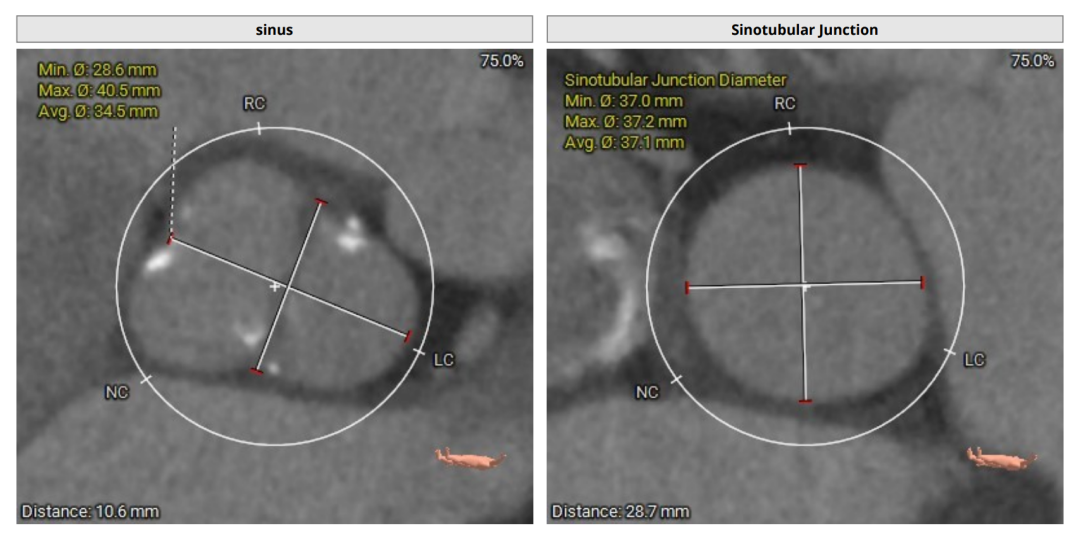

术前评估

术前CT(上下滑动查看更多图片)